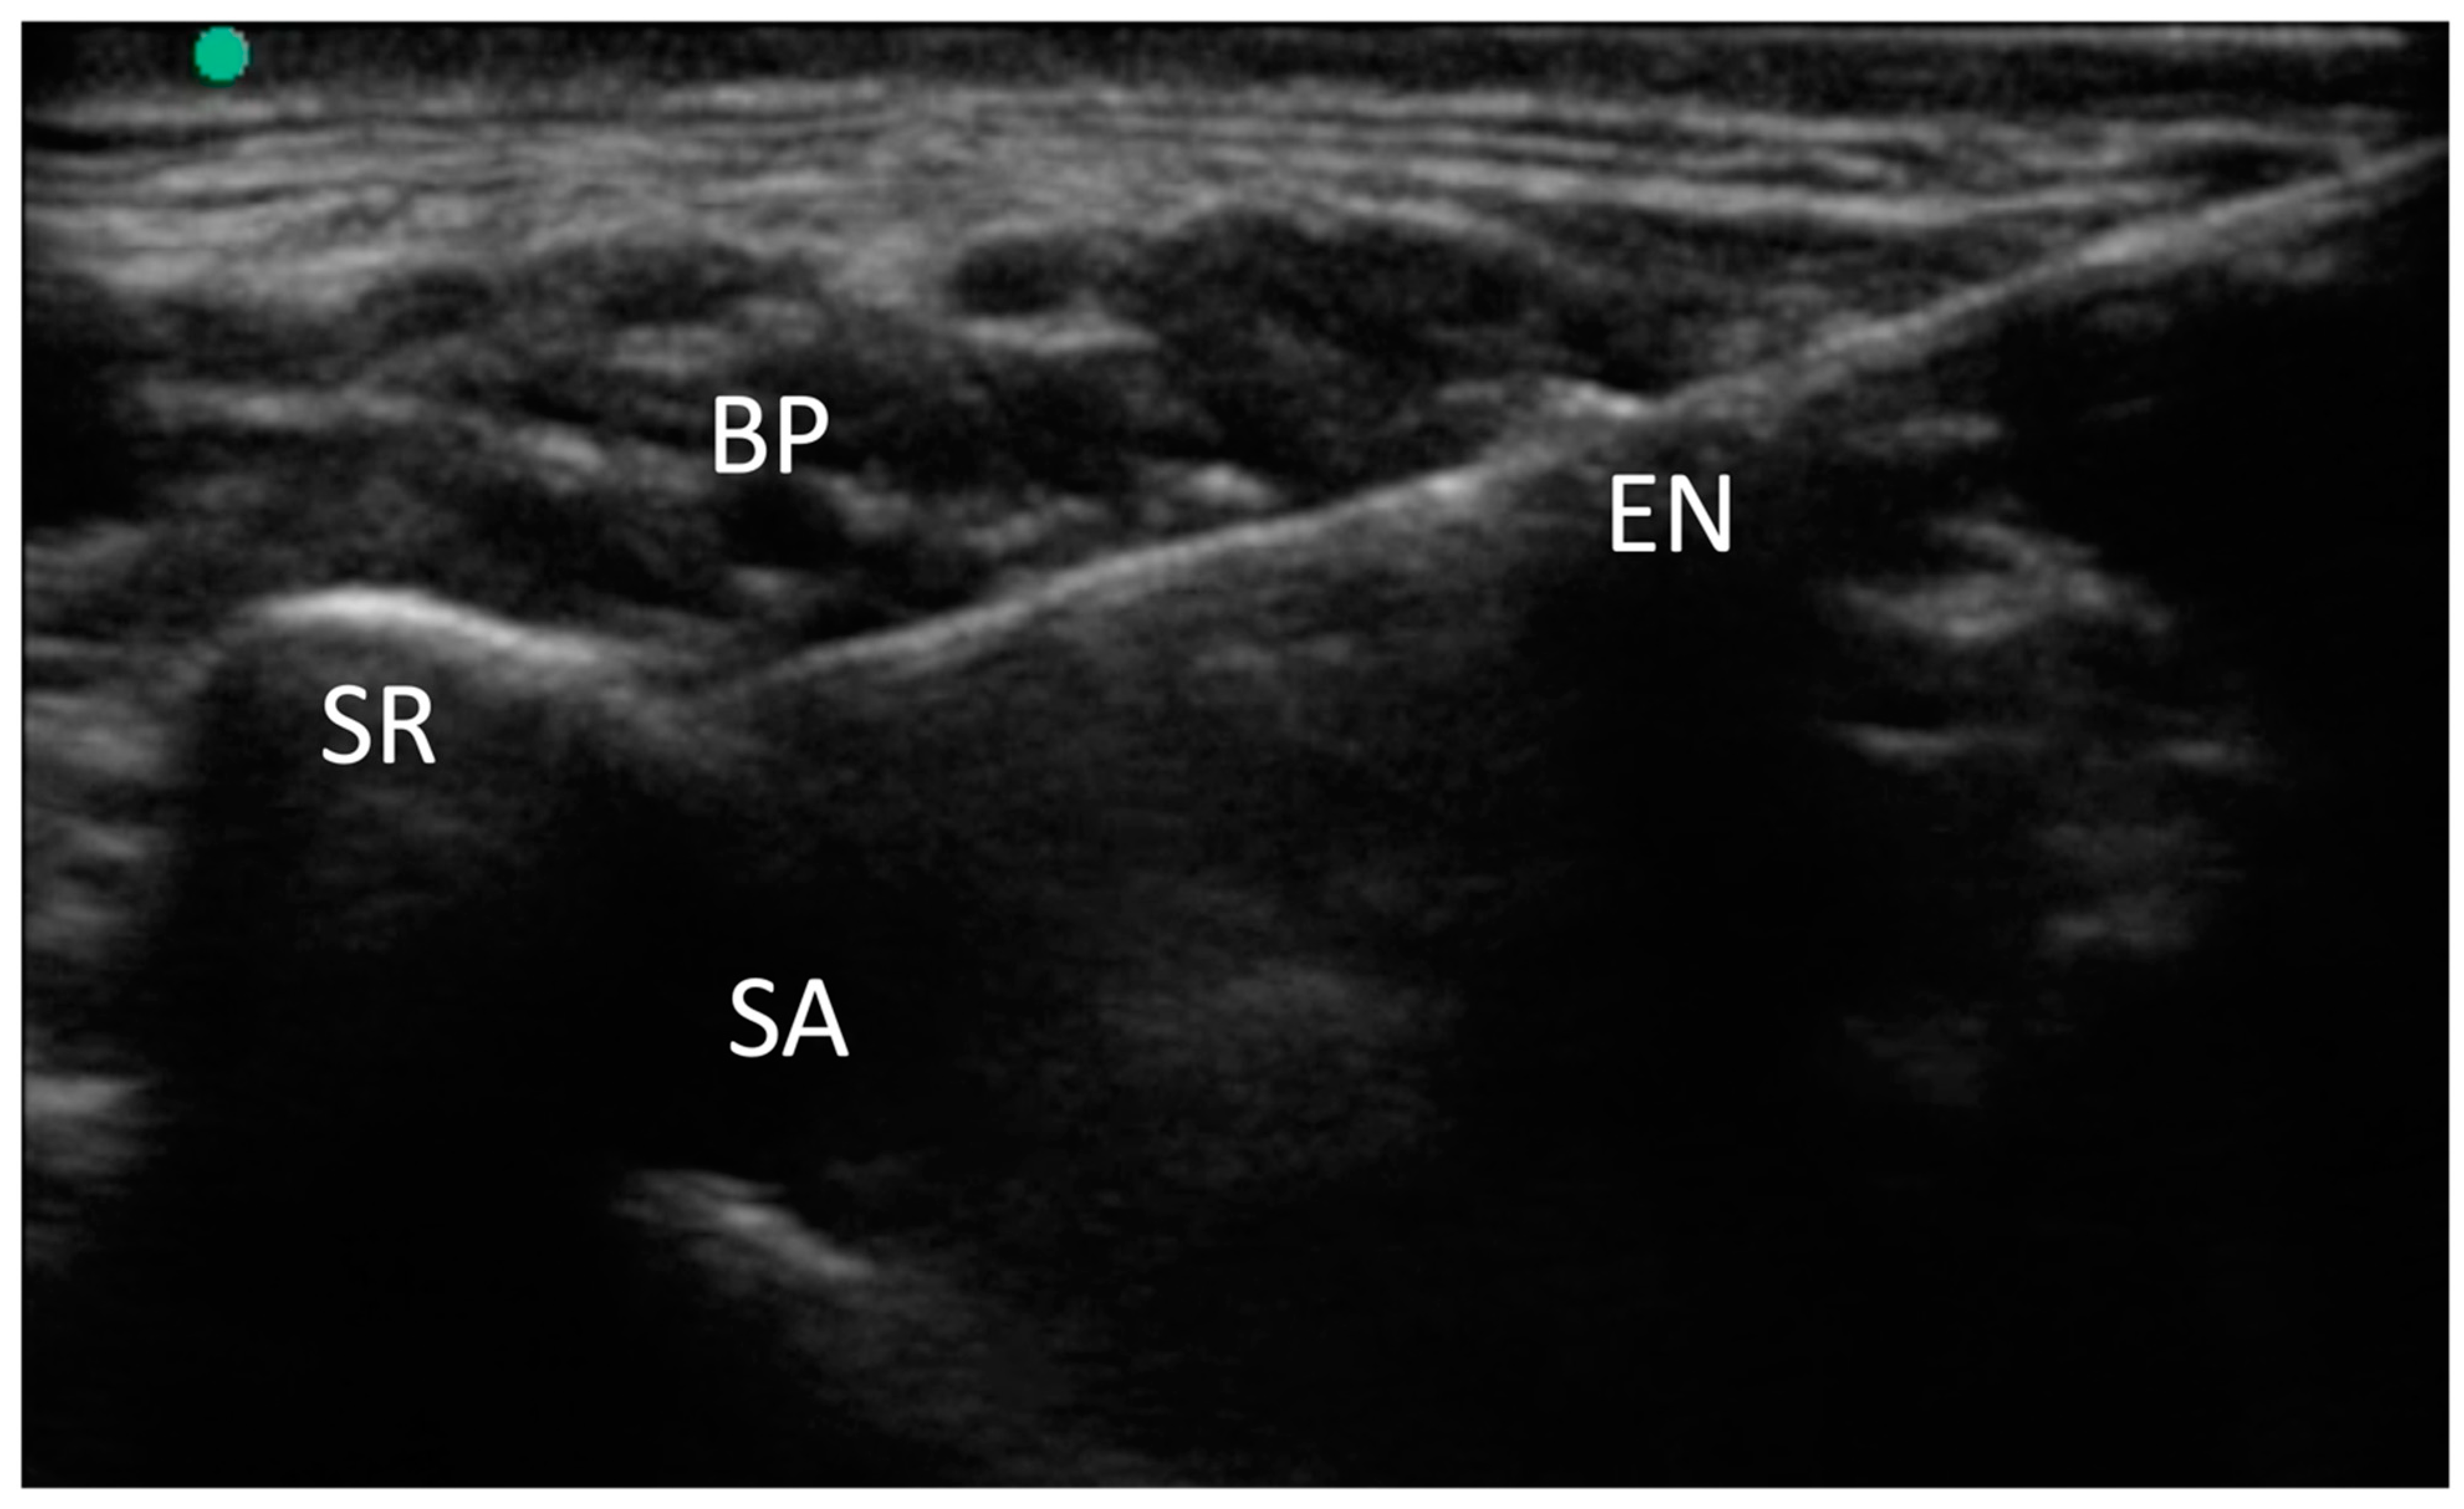

For the supraclavicular brachial plexus (SBP) block, we utilized a high-frequency linear-array transducer (M-Turbo, Fujifilm-Sonosite, Bothell, WA, USA) to visualize the supraclavicular region. We identified the brachial plexus and the subclavian artery, both situated over the first rib.

A 100 mm needle (Stimuplex Ultra 360, B. Braun, Melsungen, Germany) was then inserted using an in-plane anteromedial approach, targeting the “corner pocket,” which is the angle formed between the artery and the rib. Following this, 10 mL of 2% mepivacaine was injected, and the distribution of the local anesthetic was observed around the brachial plexus. In cases of supernumerary ribs, due to altered anatomy, the needle was positioned lateral to the subclavian artery and beneath the brachial plexus.

This medial-to-lateral needle approach facilitated access to the supernumerary rib, as illustrated in Figure 1.

Figure 1. Supraclavicular brachial plexus block. The presence of a supernumerary rib alters the normal anatomy and sono-anatomy, thereby making a medial-to-lateral approach easier. BP: brachial plexus; SR: supernumerary rib; SA: subclavian artery; EN: echogenic needle.